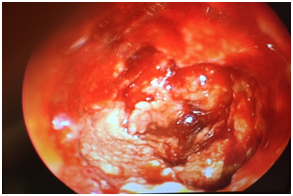

Brain MR and CT (Figure 1): Showed an expansive lesion in the left petrous apex, with well-defined contours and hyperintense signal in T1 and hypointense areas in T2, eroding the facial nerve canal, inner acoustic canal and part of the cochlea. The lower part the lesion was eroding the medial wall of the carotid canal. Additionally, it was spreading to the skull base expanding the body of sphenoid bone, sphenoidal sinus and ethmoidal cells and displacing the pituitary gland upwards.

Figure 1 Axial CT and T1-weighted MR image showing an expansive process in the left petrous apex.

It also invaded the pontocerebellar area and conditioned a mass effect over the pons of the brainstem. Because of all these signal properties as well as it location the lesion was suggestive of cholesterol granuloma as the first diagnostic probability.